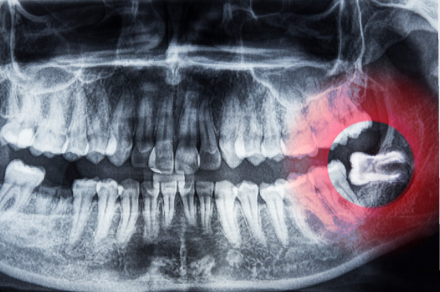

2.横向きに埋まっていて前方の歯に障害を及ぼしている

親知らずが横向きに埋まっていると智歯周囲炎や手前の第二大臼歯の吸収(歯の根が溶かされるように浸食されること)を引き起こすので、親知らずを抜くことが多いです。しかし、手前の第二大臼歯の吸収が進みすぎると注意が必要です。親知らずは生える場所がないうえに方向が悪いので普通なら抜くところですが、CTでは親知らずの手前にある第二大臼歯の根に大きな吸収が認められます。この第二大臼歯はあまりにも吸収が進んでしまったので長期的には保存できないと判断しました。この状況で親知らずを抜くと手前の第二大臼歯が将来的に失われた際に奥歯のかみ合わせが不十分となるために、入れ歯やインプラント等の治療が必要になります。幸いCTにより予め状況を把握していたので、第二大臼歯を抜いた後に部分的な矯正治療にて親知らずを正しい方向に移動して良好なかみ合わせを維持しました。ところで反対側の第二大臼歯を良く観察すると歯の根の一部に吸収した痕が見られます。奥にあった親知らずは何年も前に抜いたので手前の第二大臼歯へのダメージも少なかったのだと思われます。